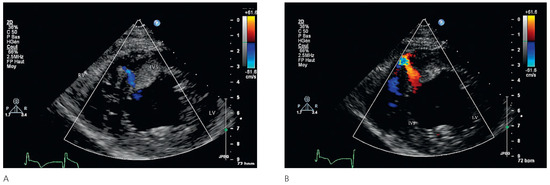

Since the first description of the athlete’s heart in 1899 by Henschen and Darling, the knowledge on cardiovascular adaptations to exercise conditioning h as expanded considerably. There is an ongoing debate about the true nature of the athlete’s hea...